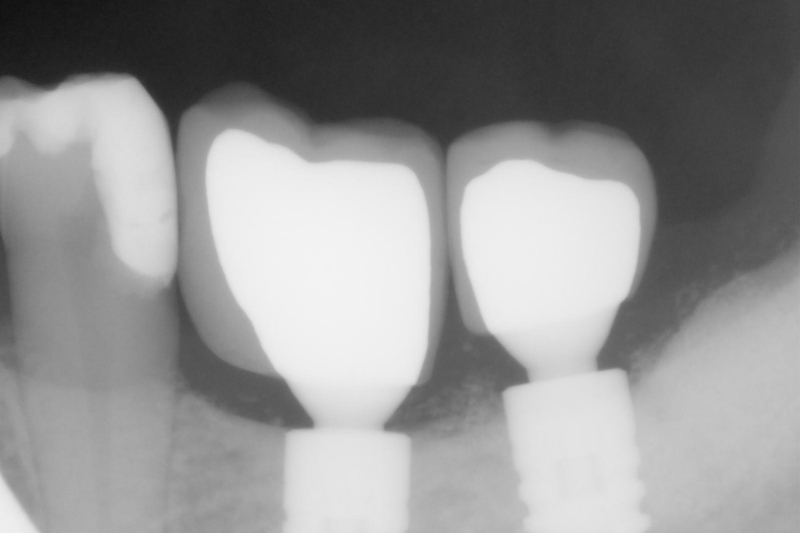

- obraz radiologiczny po zakończonej terapii